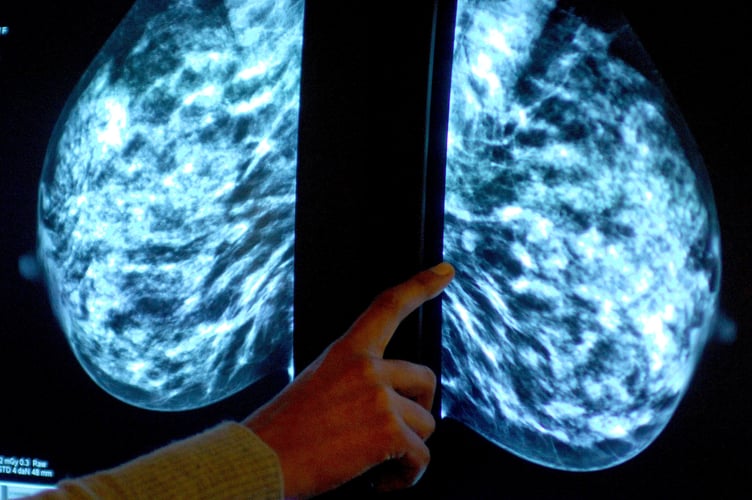

Anyone registered with a GP as female will be invited for NHS breast screening every three years between the ages of 50 and 71.

NHS England figures show 47,240 of the 72,250 people invited for a screening in the former NHS Devon CCG had a test in the year to March this year.

It meant uptake of the screening stood at 65% – down from 69% the year before, and below pre-pandemic levels of 74% in 2019-20.